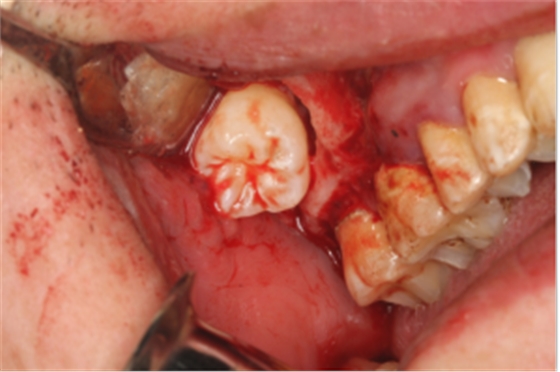

【精彩病例】